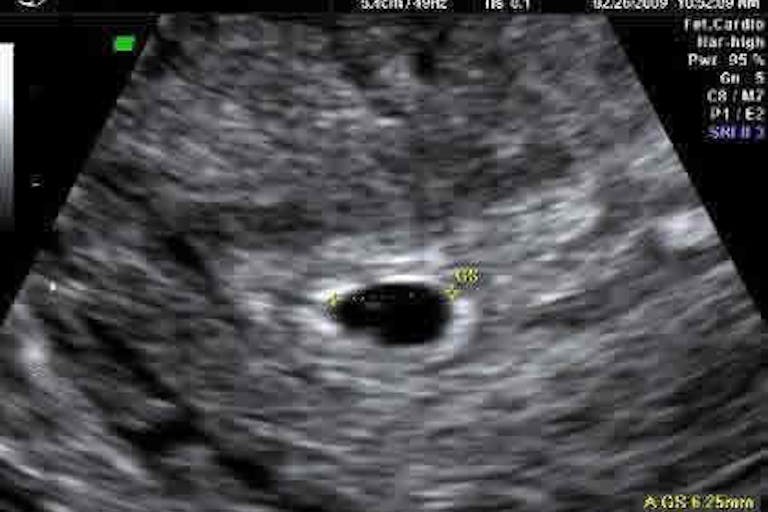

The first, and most damning, piece of evidence to come to light is that Emily Letts is a failed actress. It also turns out that the Abortion Care Network held an “abortion stigma busting competition”, which had a cash prize for the winners. And yes, her video won. Letts also claimed to be only two to three weeks pregnant — highly suspicious no matter which way you look at it. She never said whether it was two to three weeks after her last menstrual period, which would be far too early to measure a pregnancy via ultrasound. And an ultrasound is how doctors determine gestational age. So was it two to three weeks after conception, or two to three weeks after her last menstrual period? If it was two to three weeks after conception, that would actually make her about five weeks pregnant. But seeing anything at five weeks pregnant via an ultrasound is extremely difficult — yet Letts claims that she has an ultrasound photo of the baby she killed, a photo she says she will treasure forever. This is what an ultrasound would look like at the stage of pregnancy she claimed to be at: